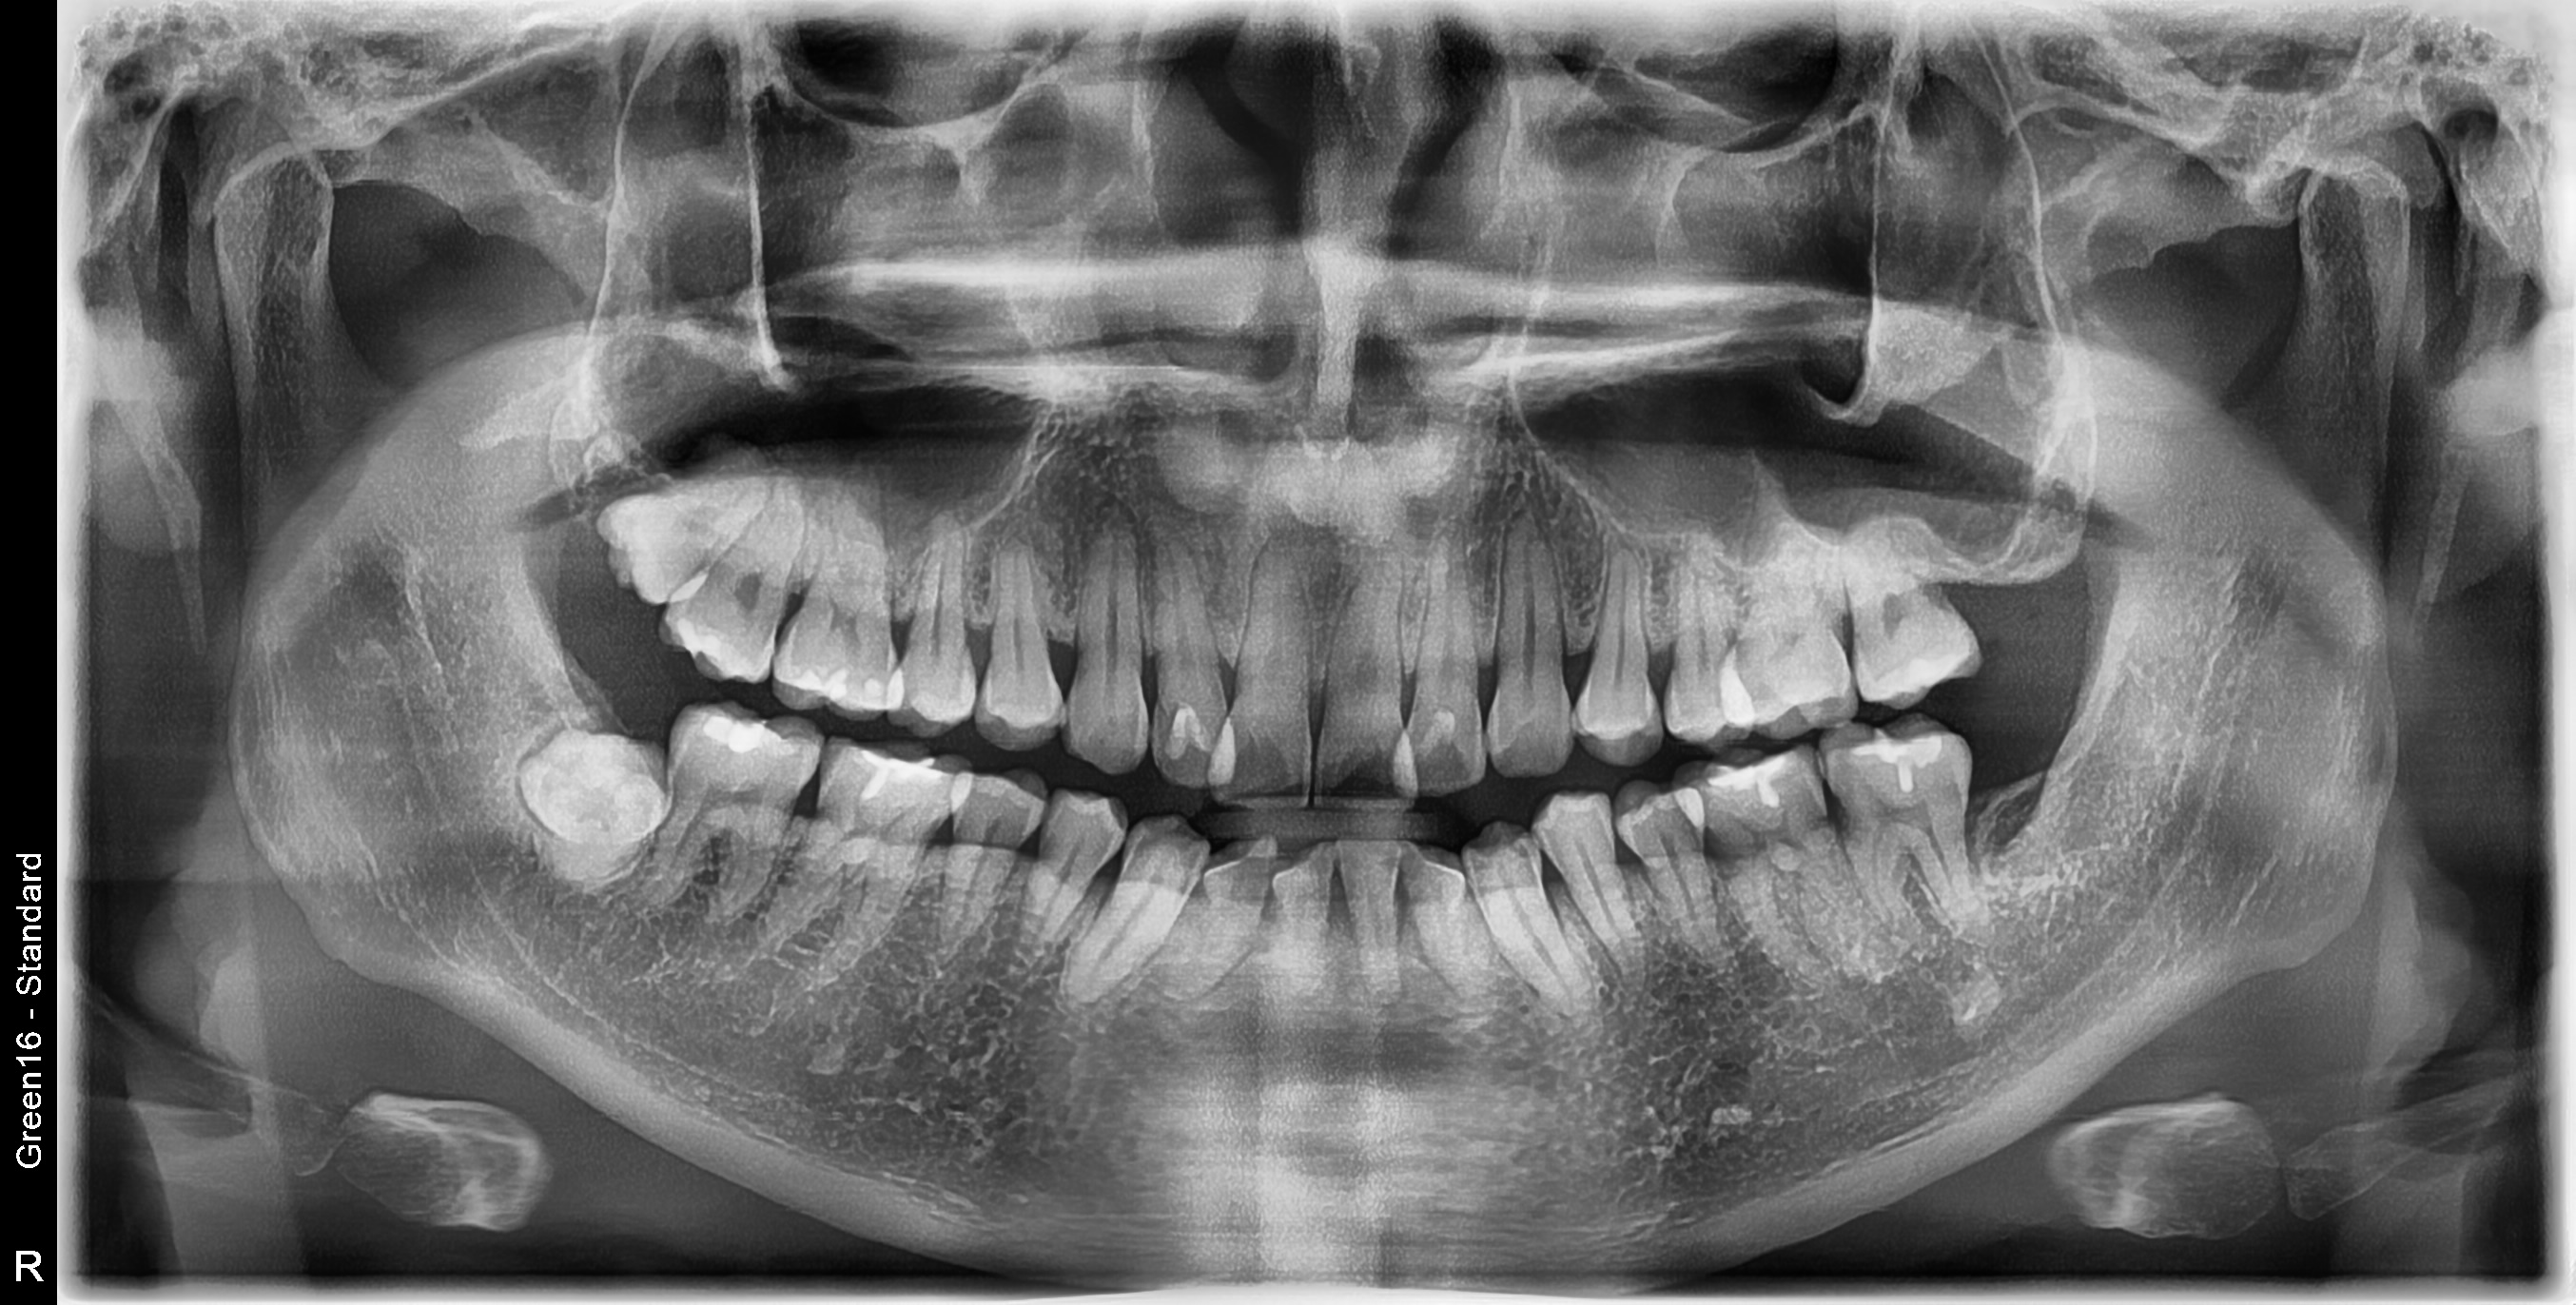

낭종, 양성종양 수술은 CT 등 정밀 검사를 통해 병변의 위치와 크기를 먼저 확인한 뒤, 주변 신경과 치아를 최대한 보존하면서 필요한 부위만 선택적으로 제거하는 치료입니다.

입 안으로 접근하거나 최소 절개로 진행해 통증과 붓기, 출혈 부담을 줄이고, 고령자나 만성질환이 있는 분들도 비교적 안정적으로 회복하실 수 있습니다.

[악안면외과] 우측 매복사랑니 발치 난케이스 사례

정확히 확인하고 깔끔하게 제거합니다.

낭종과 양성종양을 안전하게 없애는 구강 수술

낭종, 양성종양 수술은 먼저 검사로 병변의 위치와 크기를 파악한 뒤, 주변 신경과 치아를 최대한 보존하면서 필요한 부위만 선택적으로 제거하는 방법입니다. 불필요한 절개를 줄여 통증·붓기·출혈 부담을 덜어 드립니다.

수술 범위를 최소화해 회복이 빠르고 입원 기간과 내원 횟수도 줄어듭니다. 고령이거나 당뇨, 고혈압 같은 전신질환이 있는 분들도 상태를 충분히 평가한 뒤 비교적 안전하게 치료를 받으실 수 있도록 돕습니다.

Q. 구강 내 낭종·양성종양은 모두 수술로 제거해야 하나요?

낭종과 양성종양은 위치와 크기, 성장 속도, 주변 치아·신경에 주는 영향에 따라 치료 방법이 달라집니다.

뼈를 점점 부풀리거나 치아 뿌리를 밀어내는 낭종, 모양과 크기가 빠르게 변하는 병변은 보통 조직검사와 함께 제거를 고려하게 됩니다.

증상이 거의 없고 크기가 작더라도, 향후 변화 가능성을 확인하기 위해 정기적인 관찰이 필요할 수 있습니다.

최종 결정은 엑스레이·CT·임상검사 결과를 종합해 전문의가 설명드린 뒤, 환자분과 상의하여 치료 방향을 정하게 됩니다.